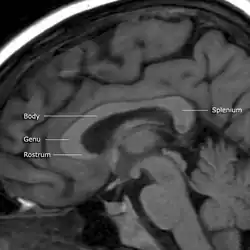

![]() Sagittal section of a brain, front part to the left. The corpus callosum can be seen in the center, in light gray | |

A number of separate nerve tracts, classed as subregions of the corpus callosum, connect different parts of the hemispheres. The main ones are known as the genu, the rostrum, the trunk or body, and the splenium.[4]

The corpus callosum has four main parts – individual nerve tracts that connect different parts of the hemispheres. These are the rostrum, the genu, the trunk or body, and the splenium.[4] Fibres from the trunk and the splenium, known together as the tapetum ("carpet"), form the roof of each lateral ventricle.[6]

The front part of the corpus callosum, towards the frontal lobes, is called the genu ("knee"). The genu curves downward and backward in front of the septum pellucidum, diminishing greatly in thickness. The lower, much thinner part is the rostrum and is connected below with the lamina terminalis, which stretches from the interventricular foramina to the recess at the base of the optic stalk. The rostrum is named for its resemblance to a bird's beak.

The end part of the corpus callosum, towards the cerebellum, is called the splenium. This is the thickest part, and overlaps the tela choroidea of the third ventricle and the midbrain, and ends in a thick, convex, free border. Splenium translates as "bandage" in Greek.

The trunk of the corpus callosum lies between the splenium and the genu.